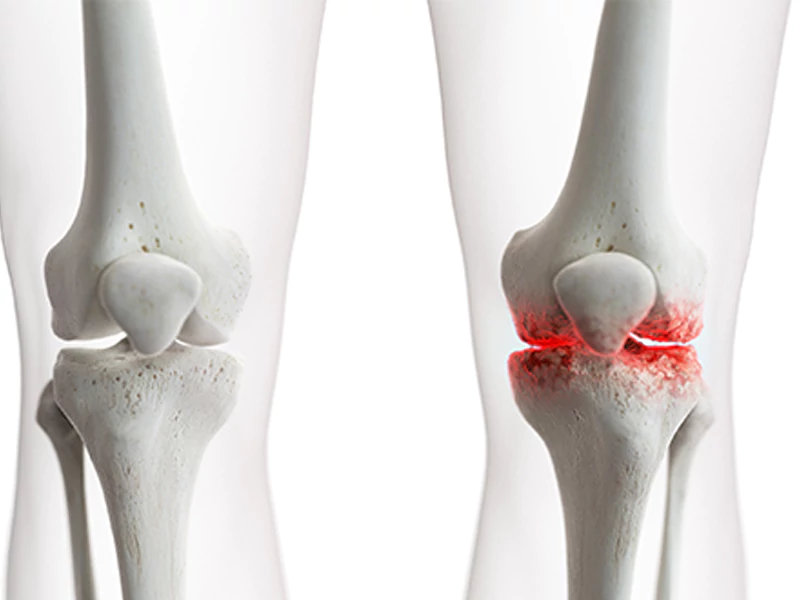

آرتروز زانو؛ بررسی علائم، علل و جدیدترین روشهای تشخیص

آرتروز زانو یکی از شایعترین بیماریهای مفصلی است که با فرسایش تدریجی غضروف زانو و درد، خشکی و محدودیت حرکت همراه میشود. این عارضه بهویژه